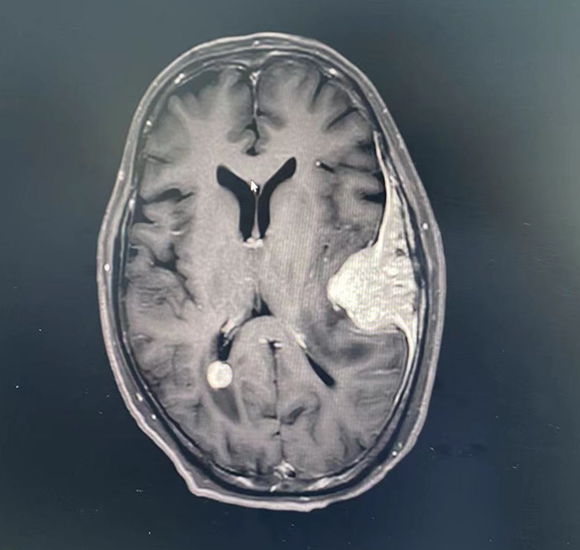

2022.05.27复查发现脑多发转移。

2022.05.30开始吡咯替尼+卡培他滨治疗(吡咯替尼400mg QD,卡培他滨片1.5g bid),患者头晕症状较前缓解,拟继续全身治疗,暂缓放疗,2022.06.08出院,2022.06.19死亡。